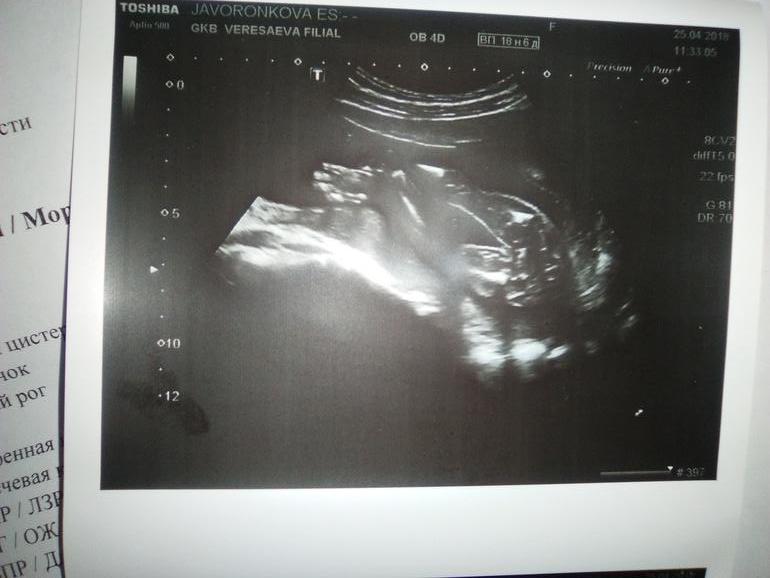

Кто тут?))

УЗИ, КТГ, доплерУ кого глаз наметан, посмотрите пожалуйста на фото, это вроде бы фото именно "того" места)))

Мне тоже кажется девочка или мальчик сильно сжал ножки и прикрыл свое достоинство)

Большинство говорят девочка, да и узист сказала "скорее всего девочка"